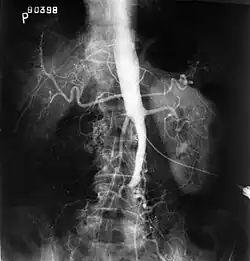

Angiography provides important information regarding the perfusion and patency of distal arteries (e.g. femoral artery). The presence of collateral arteries in the pelvic and groin area is important in maintaining crucial blood flow and lower limb viability. However, angiography should only be used if symptoms warrant surgical intervention.[2]